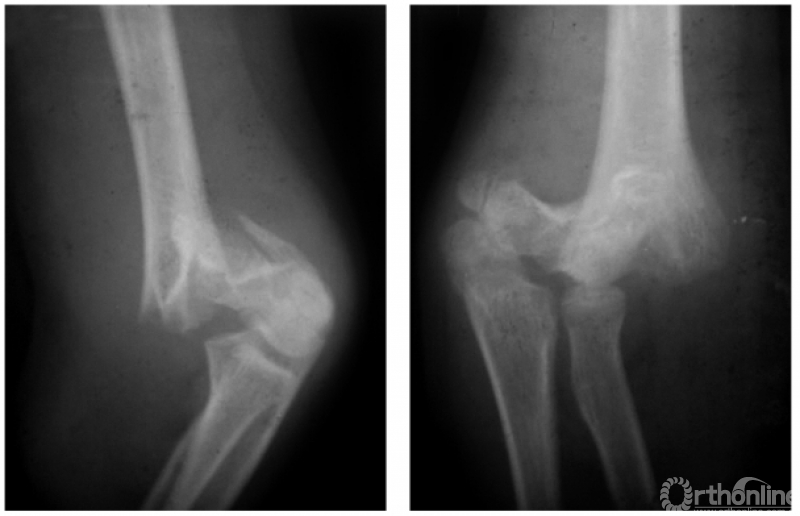

(三) 纵轴旋转型

例:髁上骨折,远折端有纵轴旋转致远近两断面的宽度很不协调(图6)。

图6